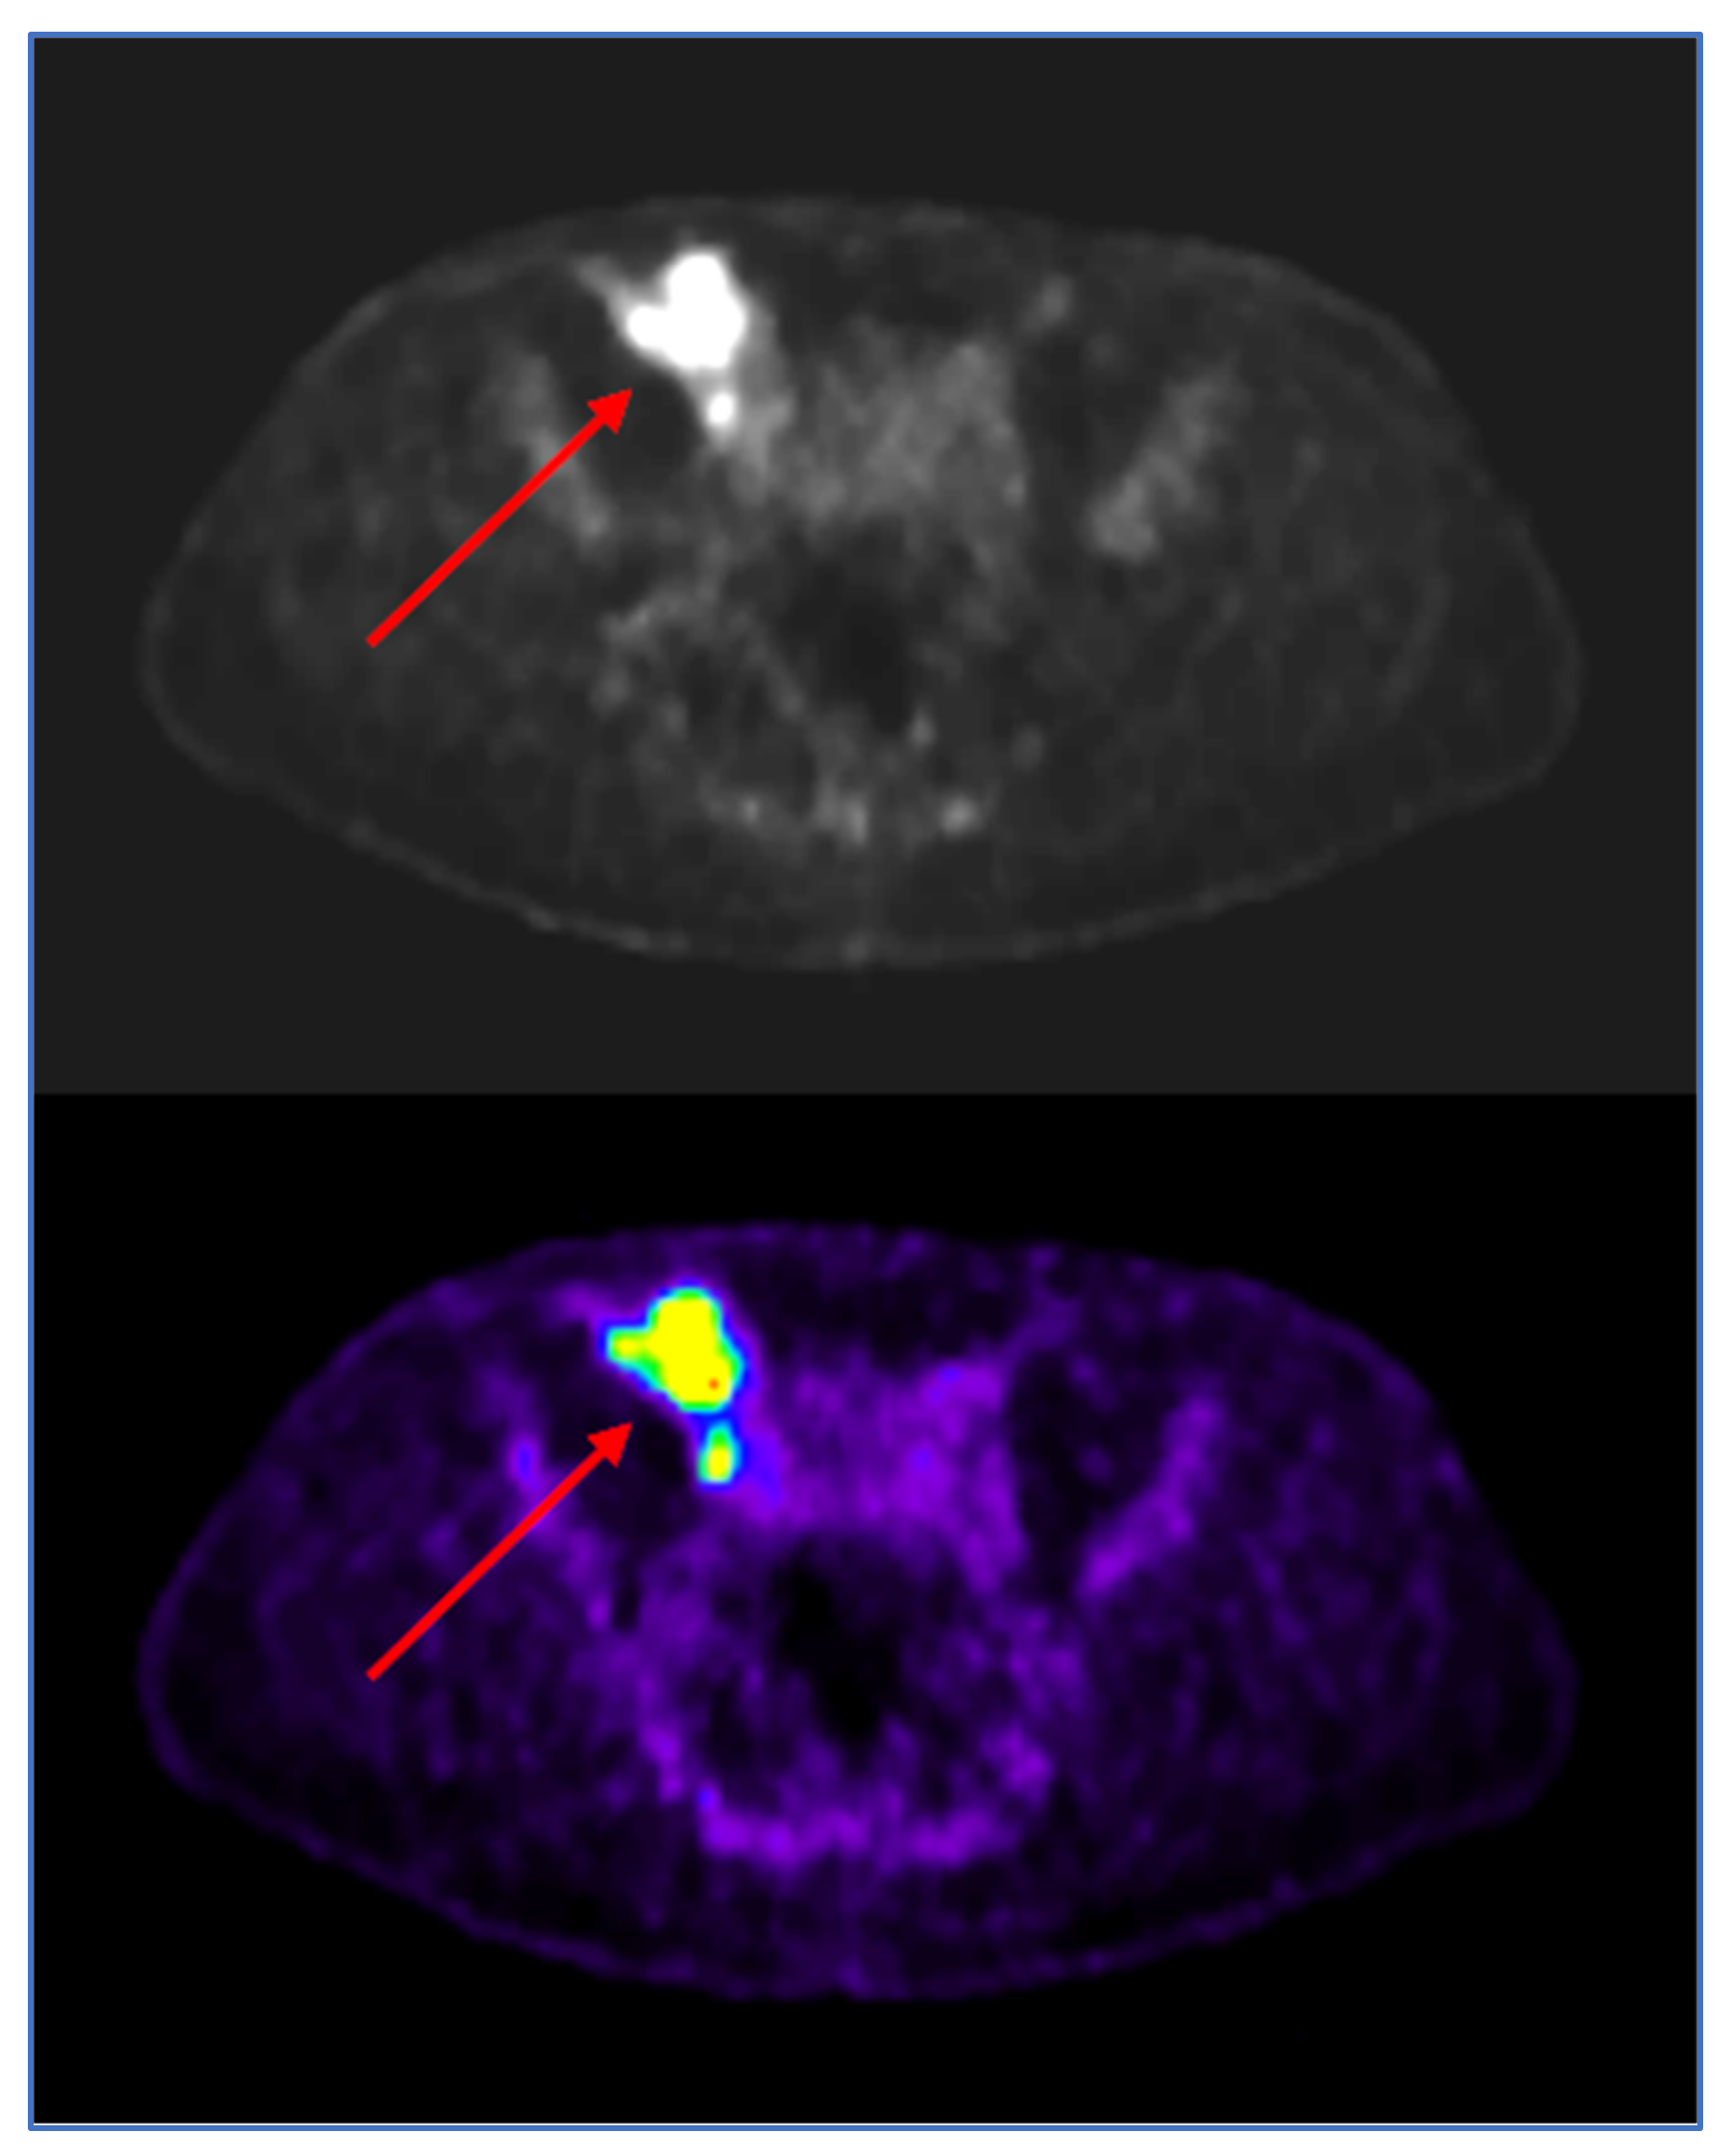

2. Case Report